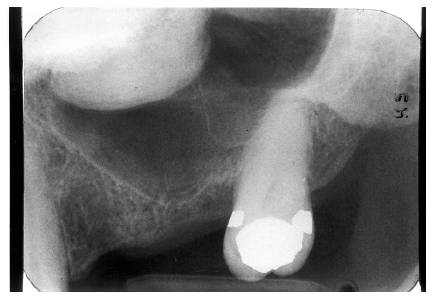

While advanced dental caries may well involve the entire tooth, early or incipient caries involves only the enamel. Once a carious lesion penetrates through the enamel, it is usually considered to be dentinal caries. Clinically, enamel caries usually appears as a stained system of occlusal grooves or as chalky white bands along the labial/buccal gingival aspects of the teeth. Radiographically, enamel caries is characterized by a focal loss of the normal enamel radiopacity, particularly on the interproximal surfaces.

It appears as a radiolucent cone shape, with the base at the exterior surface and the tip of the cone toward the pulp. The lesion follows the enamel rods. After progression into the dentin the lesion usually takes on a radiolucent fan shape.

Figure 2 illustrates advanced enamel caries on the mesial surface of the premolar.

Figure 2 - Advanced Enamel Caries

Figure 2